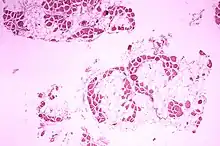

Muscular Dystrophy Histopathology

Muscular Dystrophy Histopathology.